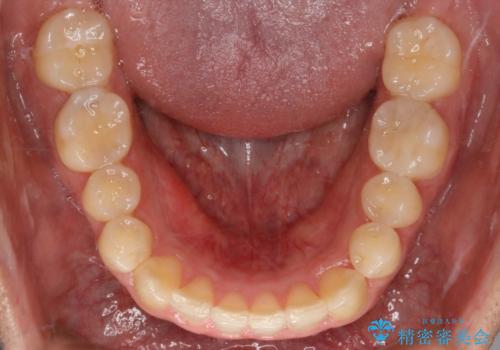

インビザラインで八重歯の治療

- 2年3ヶ月

マウスピースとマイクロインプラントを組み合わせることで、抜歯をしなくても歯並びを治すためのスペースを作ることができます。奥歯から順に移動させていくので前歯に変化が出るまでには時間がかかりますが、その分健康な歯を抜歯することなく理想的な歯並びを手に入れることができます。